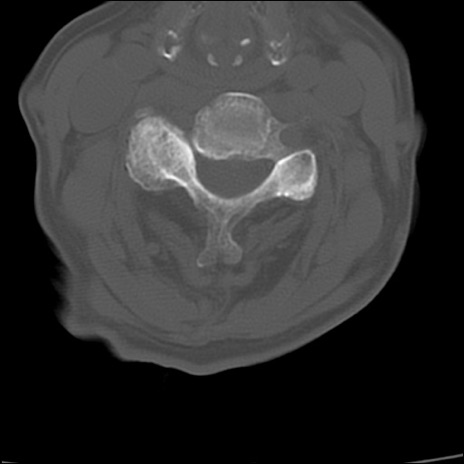

症例48 頚椎CT(横断像)

頚椎CT